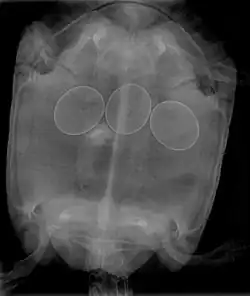

In reptiles, it is inadvisable to attempt to break a reptile egg to remove it from an egg-bound female. This procedure may be done by a veterinarian, who will insert a needle into the egg, and withdraw the contents with a syringe, allowing the egg to collapse and be removed. Non-surgical interventions include administering oxytocin to improve contractions and allow the egg(s) to pass normally. In many cases, egg-bound reptiles must undergo surgery to have stuck eggs removed.

Egg binding in reptiles is quickly fatal if left untreated; therefore, gravid females who become very lethargic and cease feeding need immediate medical treatment in order to treat the potentially life-threatening condition.